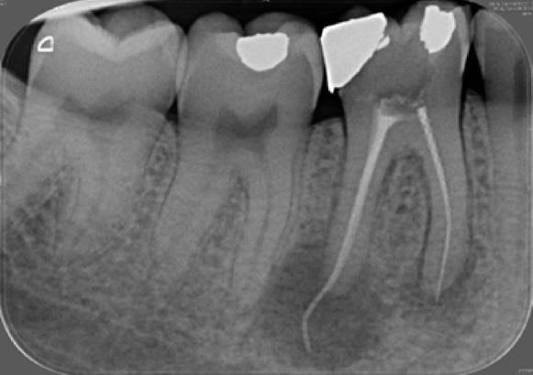

2. What Condition can be seen in this X ray regarding the tooth # 4.4.?